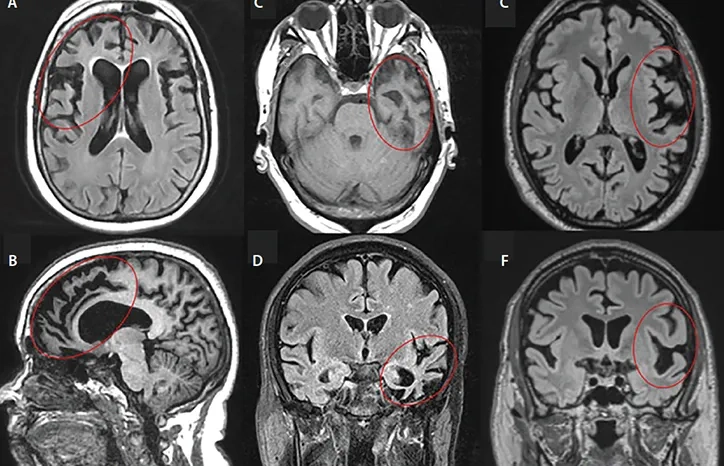

The most searched for Frontotemporal Dementia images

A visual guide to the stages of FTD

Understanding the behavioral frontotemporal dementia symptoms